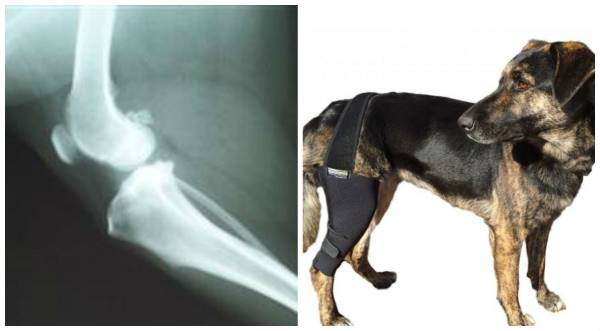

Дисплазія колінного суглоба у собак зустрічається рідко і, як правило, пов’язана з травмами. В результаті травми або неправильного утримання (слизька підлога, надмірні навантаження) суглоб частково виходить із суглобової сумки (підвивих). З-за неправильного положення суглоб б’ється і треться об краї чаші – деформація, біль, кульгавість. Така неприємність може трапитися з кожним суглобом, тому цуценя породи великої краще ростити, маючи підтримку досвідченого кінолога або заводчика.

В першу чергу ветеринар оцінить правильність і легкість рухів собаки. Потім пальпація – спроба виявити деформацію на дотик. Лікар кілька разів зігне-разогнет суглоб, щоб оцінити реакцію (є біль, хрусти, тертя тощо). Досить інформативні знімки на дисплазію, але рентген роблять тільки під наркозом. Це необхідно, щоб була можливість оцінити положення суглоба, не підтримуваного м’язами (бодрствующая собака напружується і крутиться, навіть якщо власнику і повністю довіряє лікарю).

В деяких випадках навіть на якісному фото не виходить побачити проблему цілком. Тоді бажано провести артроскопію – візуальне дослідження суглоба через прокол. Мініатюрна камера та допоміжні інструменти дозволять до найдрібніших подробиць розглянути хворий ділянку і оцінити структуру тканин. На жаль, це дорого і така послуга доступна не в кожній клініці.